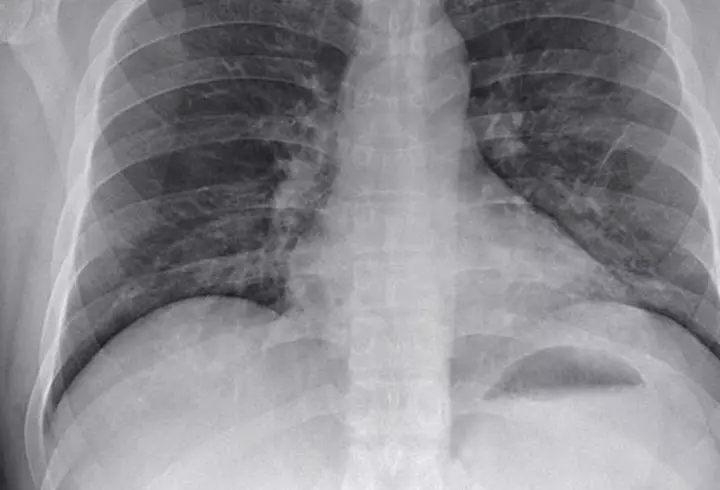

Vedete si Evenimente „Plămânul alb”, una dintre complicaţiile grave ale coronavirusului. Ce este şi ce se întâmplă atunci când apare această afecțiune